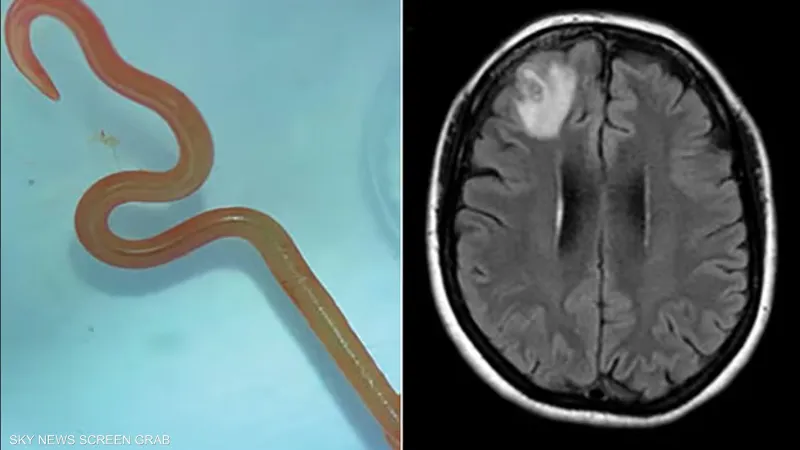

أحدث اكتشاف طبي نادر، حالة من الدهشة والقلق في المجتمع الطبي، عندما اكتشفت الدكتورة هاري بريا باندي، جراحة الأعصاب بمستشفى كانبرا، دودة دائرية حية تبلغ طولها 8 سنتيمترات في دماغ امرأة تبلغ من العمر 64 عامًا.

وسبب هذا الاكتشاف جدلًا واسعًا بين الأطباء والعلماء، خاصة بعد تحديد نوع الدودة الدائرية باسم “Ophidascaris robertsi”، وهي نوع معروف بأنه يصيب الثعابين بشكل أساسي. هذه الحالة تعتبر الأولى من نوعها عالميًّا فيما يتعلق بإصابة البشر بهذا النوع من الطفيليات.